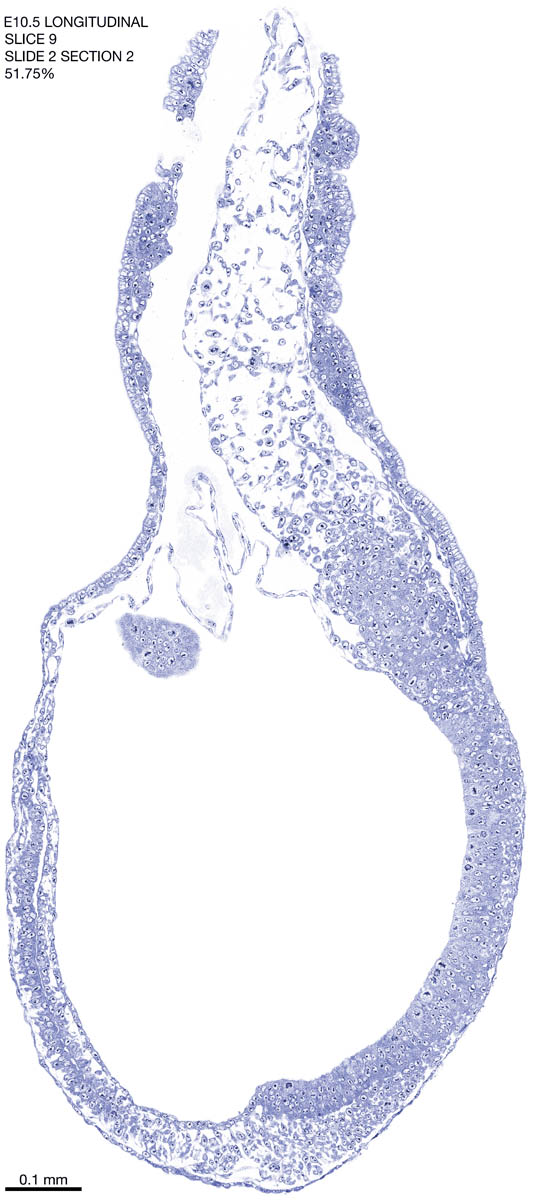

E10.5 Longitudianal Archive This page contains jpg files of ALL SLICES (each 3µm thick) that were scanned of the E10.5 longitudinally cut specimen. Download: Large | High Res Download: Large | High Res Download: Large | High Res Download: Large | High Res Download: Large | High Res Download: Large | High Res Download: Large | High Res Download: Large | High Res Download: Large | High Res Download: Large | High Res Download: Large | High Res Download: Large | High Res Download: Large | High Res Download: Large | High Res Download: Large | High Res Download: Large | High Res Download: Large | High Res Download: Large | High Res Download: Large | High Res Download: Large | High Res Download: Large | High Res Download: Large | High Res Download: Large | High Res Download: Large | High Res Download: Large | High Res Download: Large | High Res Download: Large | High Res Download: Large | High Res Download: Large | High Res Download: Large | High Res Download: Large | High Res Download: Large | High Res Download: Large | High Res Download: Large | High Res Download: Large | High Res Download: Large | High Res Download: Large | High Res Download: Large | High Res Download: Large | High Res Download: Large | High Res Download: Large | High Res Download: Large | High Res Download: Large | High Res Download: Large | High Res Download: Large | High Res Download: Large | High Res Download: Large | High Res Download: Large | High Res Download: Large | High Res Download: Large | High Res Download: Large | High Res Download: Large | High Res Download: Large | High Res Download: Large | High Res Download: Large | High Res Download: Large | High Res Download: Large | High Res Download: Large | High Res